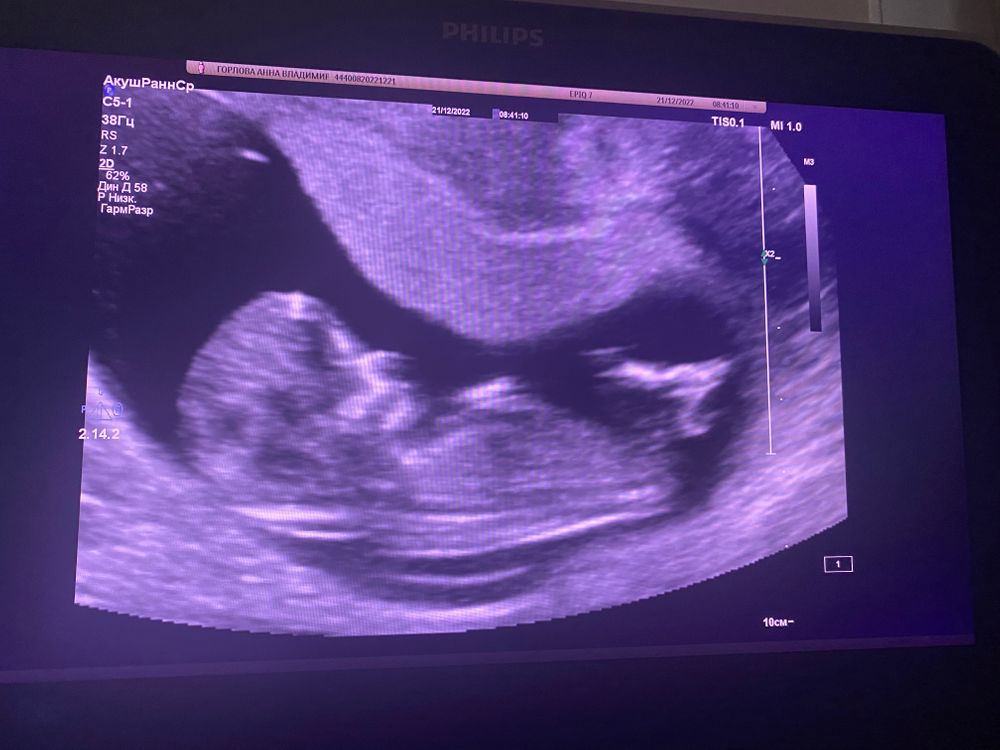

На первом скрининге по такому расположению малыша не понять, кто будет. Надо фото сбоку, чтобы был виден половой бугорок.

Annie, в общем-то, я думаю, что у вас мальчик. По форме лба на скрининге, по расположению хориона (плаценты) на этом узи.. но посмотрим, время покажет)

По форме лба похож на мальчика малыш, полового бугорка не видно чётко, а сердцебиение сходится далеко не у всех. У меня не сошлось. На 1 скрининге узистка тоже девочку предположила. На 2 я не спрашивала. Была уверена , что девочка. Но, врач сама сказала, что мальчик. Так что если чётко не видно бугорок, вилами по воде всё это. И даже с бугорками ошибаются)